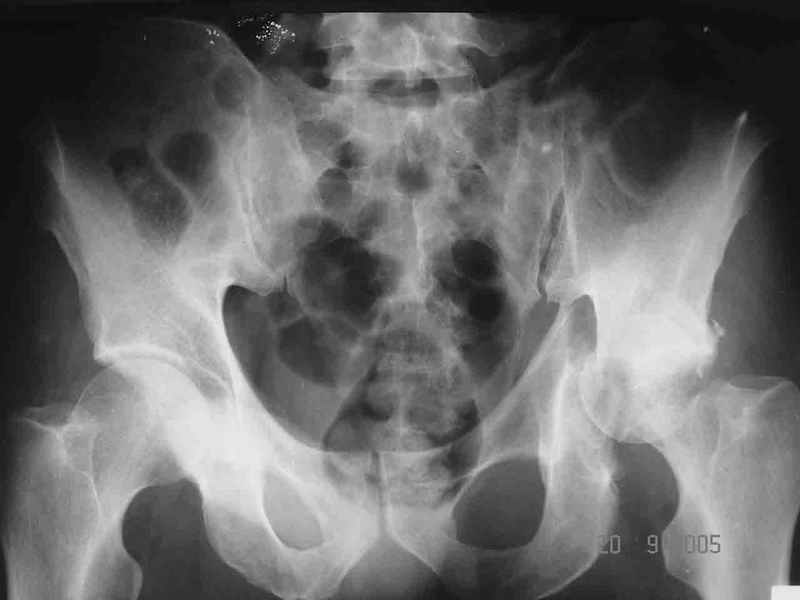

Привет! Вот недавно прооперировали похожий на ваш случай - впадина + шейка (правда у нас впадина поперечный+задний край). После травмы прошло 4 недели. мужчине 46 лет. С такой комбинацией все показания к первичному протезированию. Морально и технически мы к этому уже созрели.Но больной не собрал денег на протез. Выполнили остеосинтез впадины и шейки, прекрасно понимая, что головка вскоре рассосется, мы хотя бы надемся что к этому времени таз срастется, как говорится создали все условия для дальнейшего протезирования (может, и протез в последующем подешевле будет, в смысле, без укрепляющего кольца?). Привет Рункову!